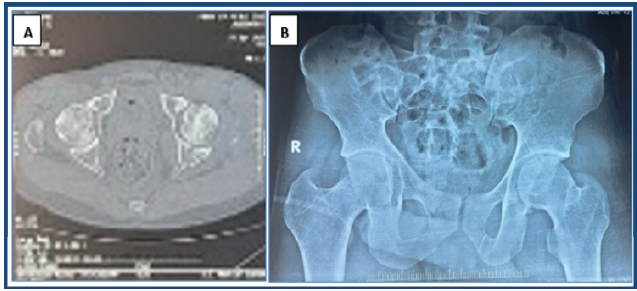

A 27-year-old male patient reported to the emergency department following a road traffic accident (motorcycle–motorcycle collision) with complaints of facial injury (laceration over scalp and ear), chest injury, pain and swelling over the left hip, and pain, swelling, and wound over the left leg (Fig. 1a).

Figure 1: Compound fracture of the tibia with posterior dislocation of the hip in a polytrauma case (a). Posterior dislocation of the left hip with comminuted fracture of the posterior wall of the acetabulum (b). Computed tomography scan showing incarcerated posterior wall fragment in the left hip joint (c).

The patient had a deformity over the left hip and left leg and was unable to walk. On, clinical examination we found that he had flexion – adduction – internal rotation of the left hip. His leg showed external rotation and abduction. There was tenderness and abnormal mobility in the left leg. In addition, there was tenderness at the left hip, and the femoral head was palpable in the gluteal region. The range of movements at the hip was grossly restricted and painful. There was no distal neurovascular deficit noted. After providing advanced trauma life support to the casualty, the patient was sent for radiography. X-rays of the pelvis with both hips and the left leg were taken. From the radiograph, we confirmed that there is a posterior dislocation of the left hip with a posterior wall fracture of the acetabulum (Fig. 1b) and a segmental fracture of the shaft of the left tibia. The patient was then taken to emergency OT and subjected to manual closed reduction of the left hip under sedation. As there was a fracture in the shaft of the tibia, the force was not transmitted to the hip joint, so we gave splintage to the leg, and the hip was reduced using the Allis maneuver. Post–reduction CT scan of the pelvis confirmed concentric reduction with femoral head congruency, minimally displaced posterior wall fragment, and intra-articular bony fragments (Fig. 1c). Since the patient had chest and facial trauma, after pre-anesthetic clearance, the patient was posted on day 2 for fracture fixation of the tibia and hip arthroscopy in the same setting. Under spinal anesthesia in the supine position, closed reduction and internal fixation of the fractured shaft of the left tibia was done using an interlocking intramedullary nail, and then the patient was put on a traction table, and left hip arthroscopy was done. Irrigation, debridement, and dynamic assessment of joint stability were performed. Hip arthroscopy revealed intra-articular loose bodies (small posterior wall fragments), which were removed, minimal chondral injury on the femoral head with intact labrum, and a stable posterior wall fracture (Fig. 2). Due to the stability of the acetabular fracture and to minimize soft-tissue injuries to the capsule and the hip, internal fixation of the fracture was not done. The patient was given below-knee skin traction to prevent abnormal hip movements.

Figure 3: Post-operative computed tomography scan (a) and X-rays (b) showing a congruous left hip joint.